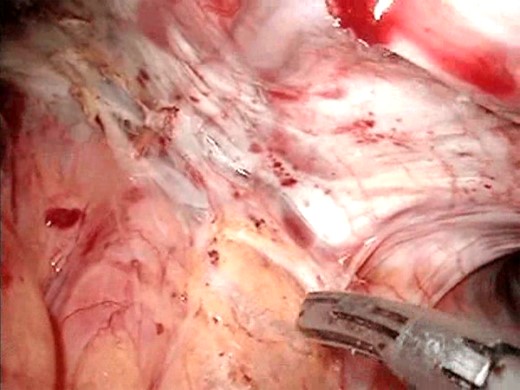

A 78-year-old Caucasian woman presented with recurrent dysphagia, slight tenderness in the epigastrium and substantial weight loss. Difficulty with solid food digestion and regurgitation were present for almost 10 years. The symptoms had exacerbated four months before intervention during which period the patient was fed through a nasogastric tube. CT scan, barium swallow (Fig. 1) and esophagogastroduodenoscopy showed a large mid-esophageal diverticulum. The neck of diverticulum was within 5 cm of the carina and was 4 cm wide. The diameter of the sac reached 10 cm, and narrow esophagogastric junction suggested achalasia, which was confirmed by manometry. The patient suffered a heart attack 3 years ago and has secondary dilatative ischemic cardiomyopathy. Due to cardiac co-morbidities, surgical intervention was graded as a high-risk procedure (ASA III), with patient’s quality of life being crucial in decision making. The patient was placed in supine position in reverse Trendelenburg with five ports placed as earlier described for transhiatal epiphrenic diverticula operations [7]. Throughout the procedure the esophagoscopic image was provided by an interventional gastroenterologist and dissection was performed under the guidance of both laparoscopic and endoscopic image (Fig. 2). This was essential due to a very narrow operating field and a lack of orientation points. The liver was retracted, and crura of the diaphragm were dissected with Ultracision (Ethicon Endo-Surgery Inc., Cincinnati, OH, USA) (Fig. 3), after which mediastinum was entered. The esophagus was bluntly dissected around its entire circumference and the gastroesophageal junction was encircled with an umbilical tape to ensure easier traction. The diverticulum was approached by both blunt dissection and electrocauterization. Resection of the wide neck of diverticulum was done with EndoGIA (Covidien, Mansfield, MA, USA) (Fig. 4). Another cartridge was used for dissection of the superior portion of the diverticulum. Possible air leakage was tested by irrigation of the field and was negative. Dissected diverticulum was withdrawn from the mediastinum and placed into an endobag. Heller myotomy was performed 5 cm orally and 2 cm distally from the gastroesophageal junction for reduction of achalasia. After the cruroplasty had been performed, the anterior fundus wall was sutured to the muscular edges of myotomy (Dor fundoplication) to prevent possible postoperative complications, such as gastroesophageal reflux disease (GERD). Operating time was 6 h, and the procedure went without any complications.

Resecting the diverticulum. The diverticulum was resected with a gastrointestinal stapler.